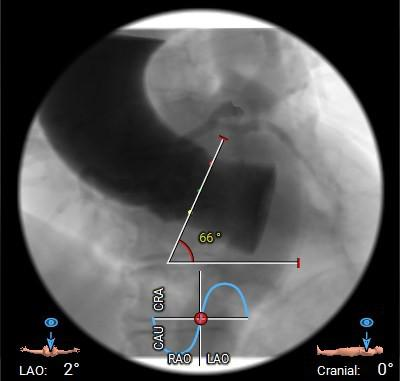

在完成术前CT扫描后发现,李阿姨入路腹主动脉严重扭曲、横位心、右冠窦无冠窦钙化融合且冠脉开口位置相对较低,左冠瓣叶冗长,术中冠脉闭塞风险高,这些不利因素均会明显增加手术的难度和风险。为此,医院迅速启动多学科协作机制,由医务处牵头,联合心血管科、麻醉科、重症医学科、血管外科、胸外科等专家团队展开会诊。经过反复讨论,专家团队最终决定采用国际先进的治疗方案一一经导管主动脉瓣置换术(TAVR)。这种微创手术无需开胸,只需通过血管穿刺即可完成瓣膜置换,极大降低了手术风险。为确保万无一失,心血管科团队还通过线上会议邀请国内知名专家对病例进行远程讨论,制定了精细化手术方案,包括入路解决方案、冠脉保护策略、术中应急措施以及术后康复计划。

▲冠脉测量

▲主动脉弓及外周入路测量

2. 腹主入路折角:双侧入路血管走形良好,整体入路血管条件一般,腹主动脉可见扭曲,经过测量33cm可以正好通过迂曲部位,也提前备好45cm长鞘,以防血管损伤。

3. 瓣膜通过性:由于横位心及大弯侧有融合脊形成台阶,瓣膜输送器通过会受影响,预备同侧snare圈套,以防无法通过。